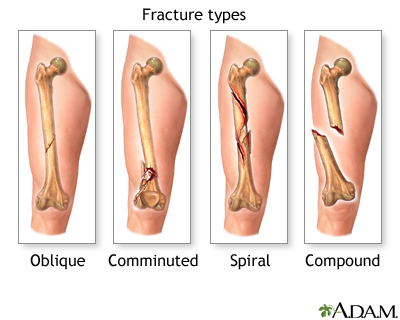

Traumatic Fracture

Trauma and Fractures | OASIS Orthopaedics Melbourne Traumatic Injury & Fracture Treatment - My Toronto Physio Traumatic Spine Fracture - Goodman Campbell All Types of Fractures & Trauma - Dr. Prajaktam Lende's Niva Ortho Care | Orthopedic Surgeon In Nagpur | Orthopedic Doctor in Nagpur | Traumatic Fracture